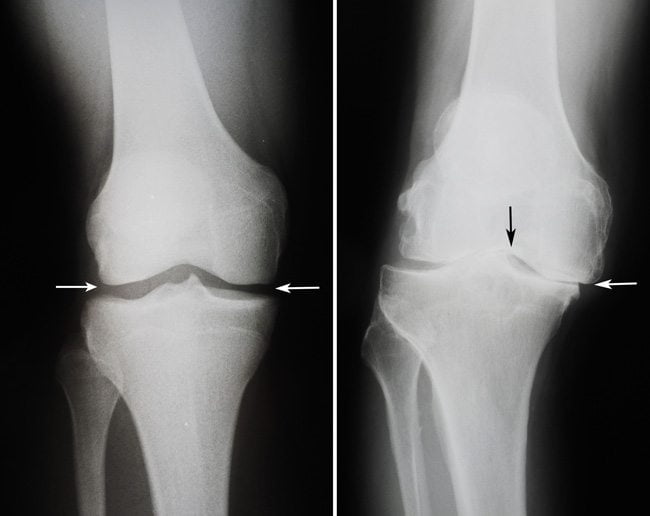

| Двухсторонний гонартроз 1 степени | Во время движений может наблюдаться не выраженная крепитация. Сам сустав еще не деформирован. Человек передвигается без вспомогательной опоры. На снимках рентгена врач может увидеть небольшое сужение в суставной щели. Двусторонний артроз коленного сустава 1 степени приводит к ощущению повышенной утомляемости в ногах |

| 2 степень | При переходе болезни во вторую степень человек ощущает первые боли (стартовые). При сгибании ног больной замечает скованность. На снимках рентгена, помимо сужения суставной щели, специалист может выявить костные остеофиты. Двусторонний гонартроз 2 степени приводит к атрофированию мышц бедра |

- рентгенография пораженных суставов;